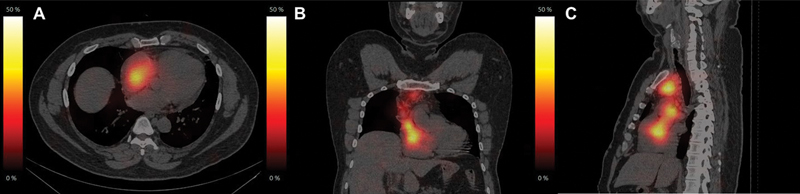

A unique case of papillary carcinoma of the thyroid with an extensive tumor thrombus extending into the right ventricle is presented. The patient was a known case of solid variant of papillary carcinoma of thyroid, post three cycles of radioiodine therapy, had reported for a diagnostic 131 I-NaI scintigraphy as a part of the workup for planning the next 131 I therapy. Clinically, the patient was asymptomatic. 131 I-NaI scintigraphy showed an arcuate pattern concentration of tracer in the upper mediastinum, which descended up to the lower mediastinum. A 131 I-NaI single photon emission computed tomography/computed tomography (SPECT/CT) showed a tracer avid tumor with an extensive tumor thrombus extending from the left brachiocephalic vein to the right ventricle. 18 F-fluorodeoxyglucose positron emission tomography/computed tomography ( 18 F-FDG-PET/CT) and magnetic resonance imaging (MRI) demonstrated similar findings. The patient was decided to be managed with tyrosine kinase inhibitors as surgical intervention was not deemed possible due to the involvement of major vessels and the high risk of bleeding.